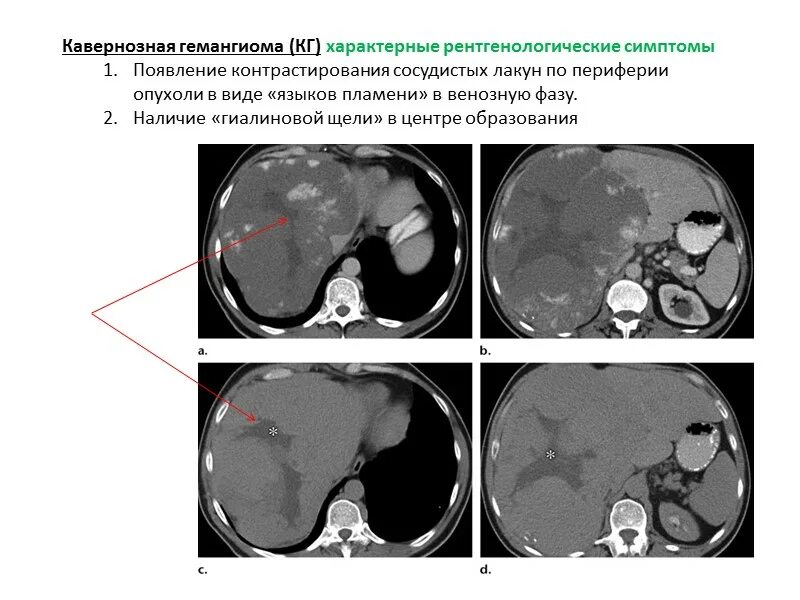

Образования печени кт